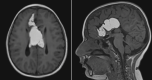

[Atypical growth of an intracranial lipoma]